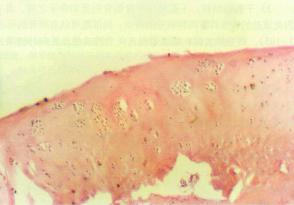

顱骨結核大體可見在與受累的顱骨相應部位的頭皮下有寒性膿腫,內含乾酪樣壞死組織及至膿腫破潰後形成的竇道。顱骨呈棕灰色,無光澤,質鬆軟常有形狀不同的骨缺損或死骨。顯微鏡下可見皮下及竇道內和硬腦膜外有大片乾酪樣壞死及纖維結締組織增生,顱骨的骨小梁正常結構遭到破壞,分辨不清。